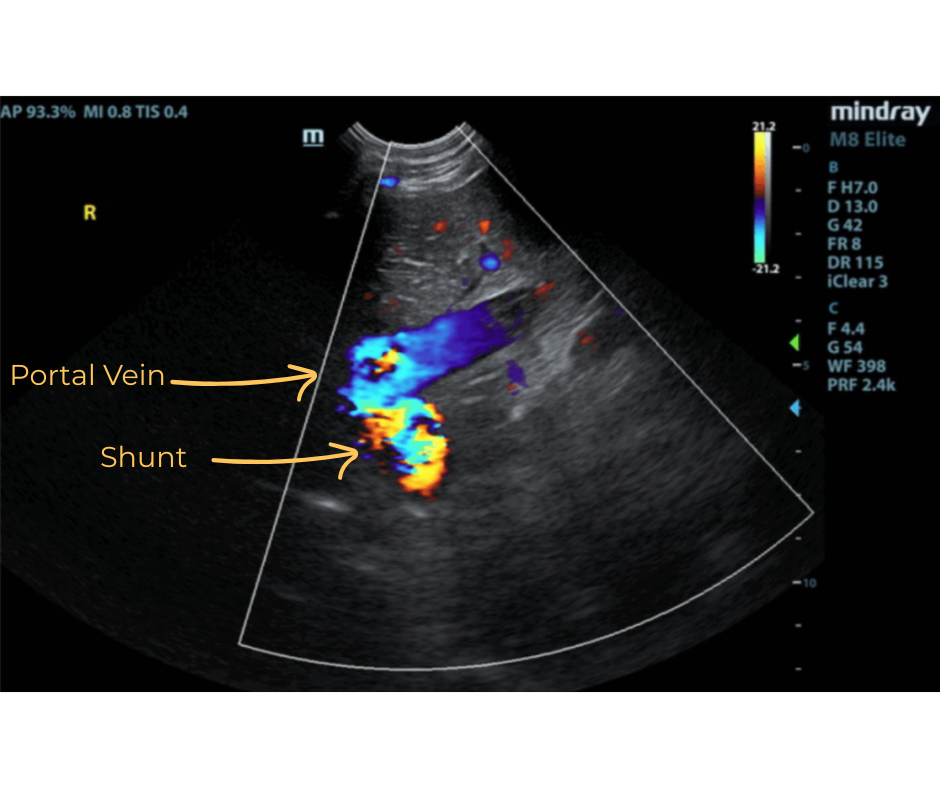

The liver was subnormal in size. The mid dorsal liver in this patient revealed an abnormal intrahepatic branch of the portal vein. This is most consistent with central divisional shunt. However, this should be further evaluated with CT. The gallbladder and common bile duct were unremarkable.

- Intrahepatic shunt – suspect central divisional or right divisional shunt

- Suspected Intrahepatic Shunt

Ultrasound can identify a small liver, abnormal vessels, altered portal vein/vena cava ratio, altered portal vein/aorta ratio, renomegaly, and urolithiasis. Identification of an IHPSS with an experienced operator has a sensitivity of 95-100%. IHPSS tend to have a large diameter and they are outlined by the liver parenchyma making them easier to identify. CT scan is used for cases that are unable to be identified using ultrasound and to correctly identify the origin and end point of the shunt for surgical planning.